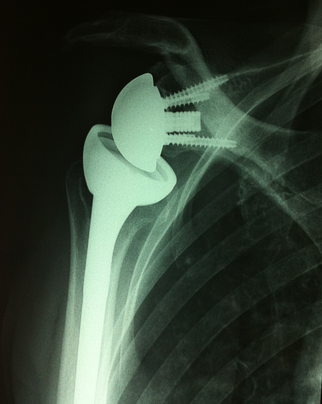

Prothèse totale d'épaule inversée. Notez le design de la prothèse qui est différent

Prothèse totale inversée

On appelle ainsi cette prothèse car la partie sphérique de la prothèse est positionnée sur l'omoplate et la partie concave sur l'humérus (cf photo ci-contre). Ce type de prothèse est utilisé en cas de lésion importante et non réparable de la coiffe des rotateurs ou encore en cas de reprise de prothèse (changement de prothèse) ou lorsque la glène de l'omoplate est très déformée.